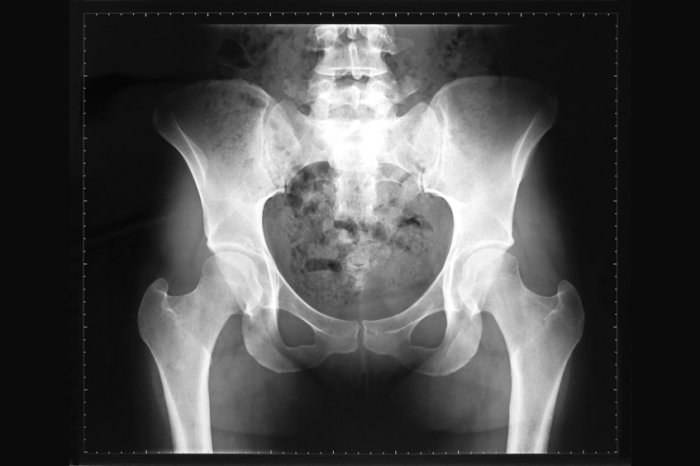

Radiologicamente, a lesão apresenta frequentemente o aspecto clássico em “vidro fosco”, devido à mistura de matriz fibrosa e mineralização incompleta, embora esse padrão possa variar conforme a idade do paciente e a fase evolutiva da lesão.

Na forma poliostótica, os sintomas são mais evidentes e podem incluir dor crônica, deformidades esqueléticas e discrepâncias no comprimento dos membros. Uma deformidade característica é o encurvamento progressivo do fêmur proximal, conhecido como deformidade em “báculo de pastor”, resultante da fragilidade estrutural do osso.

Os ossos mais frequentemente afetados incluem costelas, fêmur, tíbia, ossos craniofaciais e pelve, enquanto o envolvimento das mãos, coluna e esterno é menos comum.

O diagnóstico baseia-se principalmente em exames de imagem, associados à avaliação clínica. A radiografia simples é geralmente o exame inicial e pode mostrar uma lesão com aspecto clássico em “vidro fosco”, associada à expansão óssea, adelgaçamento cortical e deformidade estrutural, sem características agressivas típicas de tumores malignos.